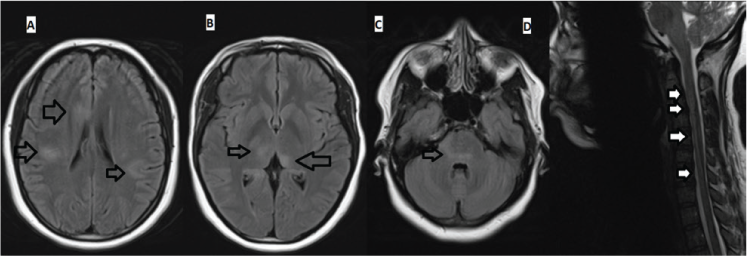

Magnetic resonance imaging (MRI) of the brain (done without contrast due to her pregnancy) showed abnormal increased T2-weighted and fluid-attenuated inversion recovery signal involving the cortex, subcortical white matter, bilateral thalami, and brainstem (Figure 1). There were no abnormal findings on T1- or diffusion-weighted images.

Axial fluid-attenuated inversion recovery magnetic resonance images (MRIs) of brain and sagittal T2-weighted MRI of cervical spine before treatment

Noncontrast MRI of the cervical spine showed vague longitudinally extensive hyperintense signal on T2-weighted and short-T1 inversion recovery images overlying the upper cervical cord extending to the medulla. There were no abnormal findings on T1-weighted images. No MRI of the thoracic and lumbar spine was performed.